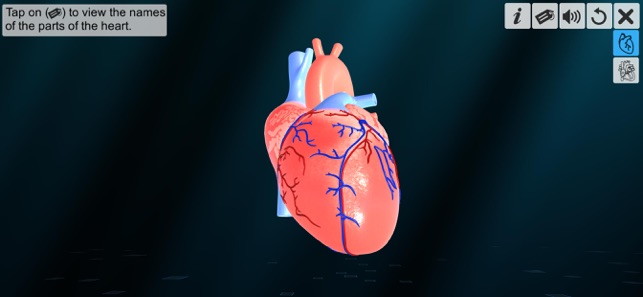

‘Heart - An incredible pump’ app provides a sneak peek into the amazing pumping organ of the human body – the heart.

1. Full heart introduction.

‘Heart - An incredible pump’ app explains the external and internal structure of human heart through the simulation 3D model to improve the comprehension of the topic. The user can interact with the 3D model by tapping the model and getting acquainted with the particular part of the human heart. Tapping the model displays the name of the part and also the simulation module is appropriately supported with in depth information about each external and internal structure part.